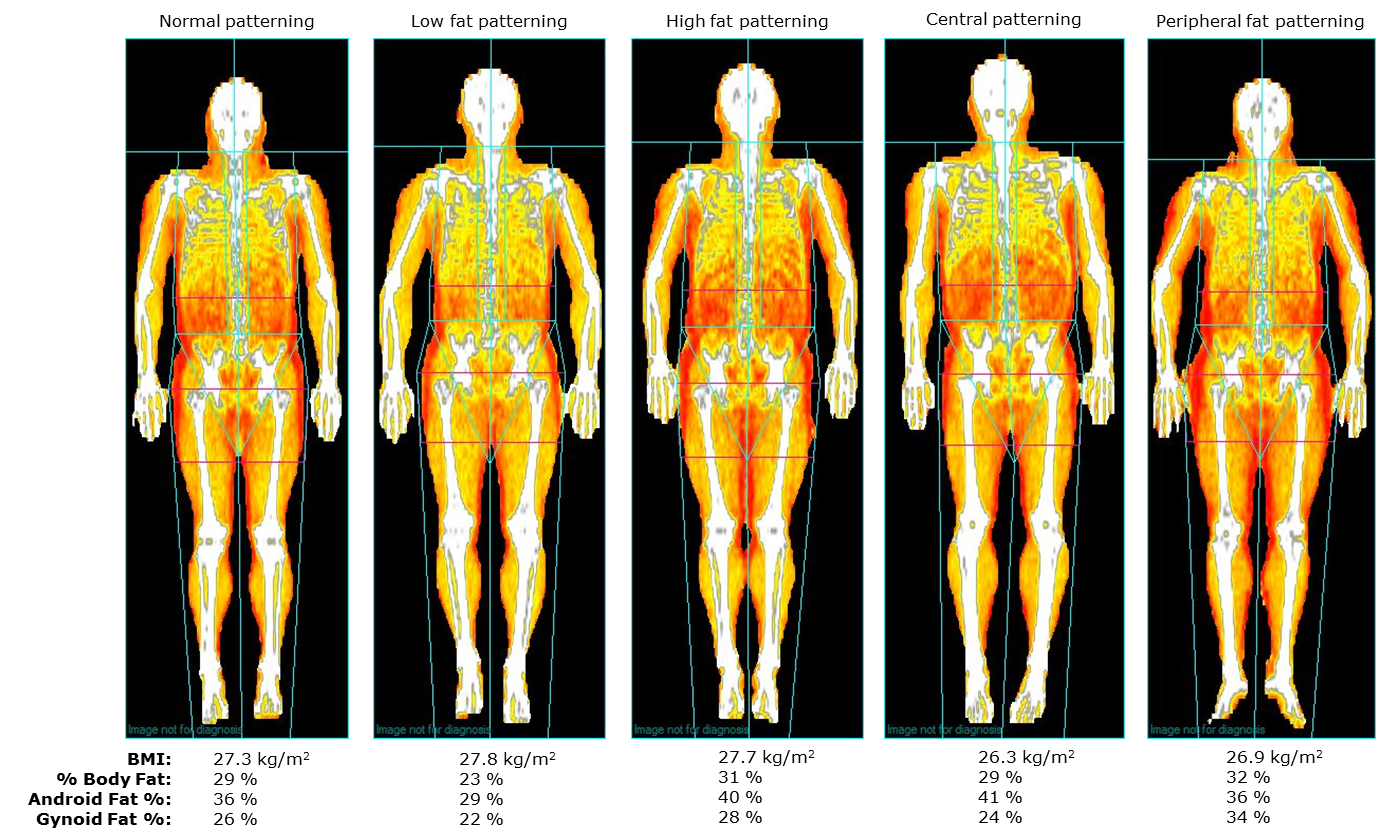

His work here is focused on optimising heath over a person’s lifespan using modern tools such as blood-work analysis, VO2 and Dexa scans. More recently, Alan has also been involved with the hugely popular fitness app, LEAN with Lilly, acting as the sole nutritionist for the app with hundreds of thousands of users.